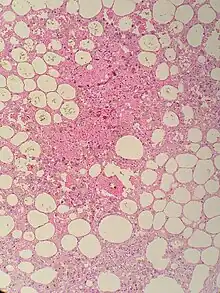

| Sclerosing mesenteritis - note the hemosiderin, chronic inflammation | |

The disorder is identified by histopathology showing fat necrosis, fibrosis and chronic inflammation of the small intestine. Examination of the mesentery may indicate a solitary mass, but diffuse mesentery thickening is common.[4][6]